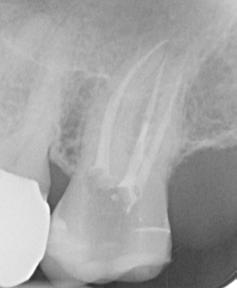

The preoperative radiograph (Figure 10) shows tooth 27 already trephined by the previous practitioner. The root filling appears inhomogeneous. The root filling material in the mesiobuccal canal is extended beyond the radiographic apex and there is periapical osteolysis of the mesiobuccal root.

The revision treatment was carried out in two sessions. After placing the rubber dam, the temporary filling was removed, and the access cavity was cleaned. This was followed by intracoronal diagnostics (figure 11). Bacterial colonized root filling material was found in the mesiobuccal, distobuccal and palatal canals.

The orifice of the mesiobuccal canal was widened in the palatal direction. Removal of a mesial dentin overhang with a long-shaft round bur exposed the orifice of the second mesiobuccal canal, which was displaced far in the palatal direction.